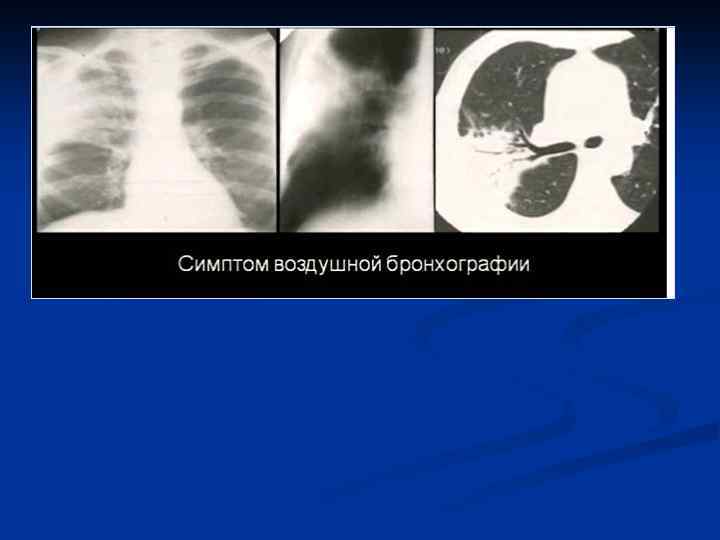

КТ–семиотика плевропневмонии – прямые признаки n n Уплотнение легочной ткани Симптом «воздушной бронхографии» Уменьшение объема Плевральные изменения

Плевропневмония